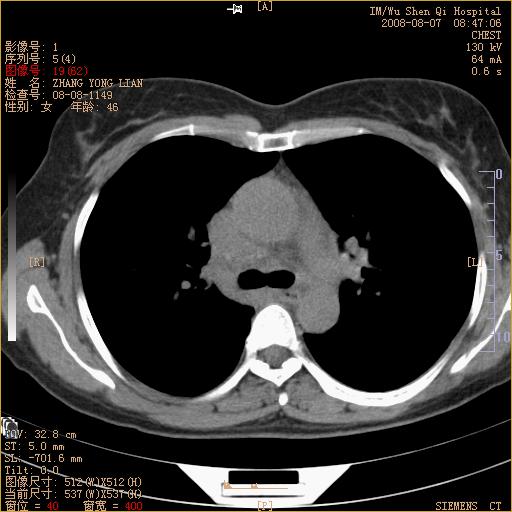

标题: CT15050:女,46岁,咳嗽胸痛一月余 [打印本页]

纵隔窗没发全,左下肺近胸膜处结节。有长毛刺,纵隔淋巴结增大,不排除恶性病变。

考虑肺癌

考虑左肺下叶后基底段周围型肺癌伴纵隔淋巴结转移可能性大。

左下肺ca并纵隔及左肺门区淋巴结转移。

脾脏低密度结节转移不排除。

1)考虑左肺下叶后基底段周围型肺癌伴纵隔淋巴结转移。2)脾内低密度灶,性质待定;不排除转移瘤可能。

考虑左肺下叶后基底段周围型肺癌伴纵隔及肺门淋巴转移。